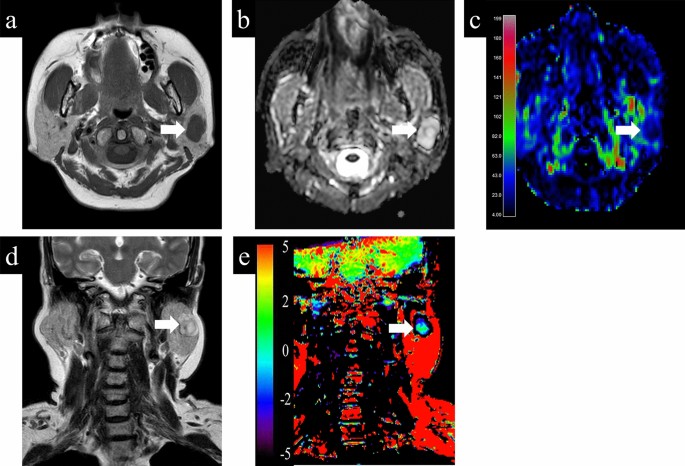

Representative cases with parotid gland lesions are shown in Figs. 4, 5, 6. Typical pleomorphic adenomas show low TBF, which makes it difficult to distinguish from malignant lesions, while present high ADC and low APT which suggest benign lesions (Fig. 4). On the other hand, Warthin tumors have low ADC, which makes it difficult to distinguish from malignant, while presenting high TBF and low APT, which is consistent as benign (Fig. 5). Most malignant lesions showed high APTSI, low ADC, and moderate TBF (Fig. 6).

A 68-year-old female with pleomorphic adenoma. (a) T1-weighted image shows a homogeneous low intensity lesion in the left parotid gland. Apparent diffusion coefficient (ADC) (b) and tumor blood flow (TBF) (c) maps show the lesion with the mean ADC value of 1.88 × 10−3 mm2/s and the mean TBF value of 22.55 mL/100 g/min, respectively. On T2-weighted coronal image (d), the lesion shows higher signal intensity than the adjacent parotid gland parenchyma. Amide proton transfer (APT) (e) map shows the lesion with the mean APT-related signal intensity of 0.26%. An arrow in each image indicates the lesion.